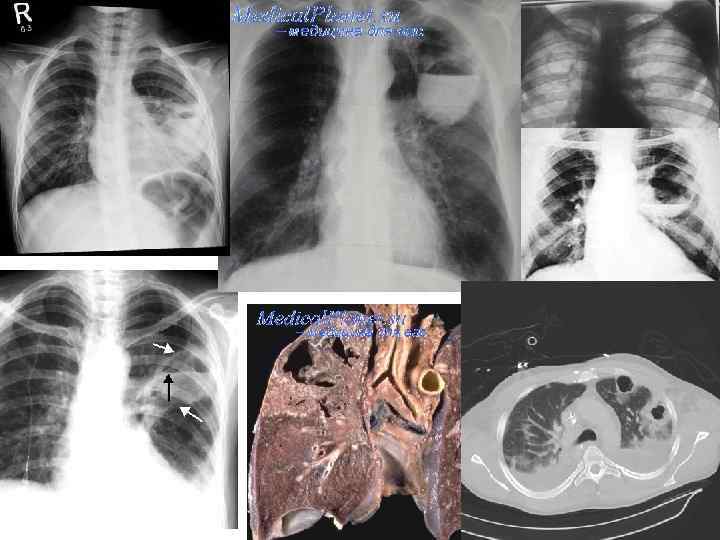

<<<< Перейти к списку синдромов - Наличие полостного образования (образований), имеющих стенку, окруженную инфильтратом или фибрознойтканью (абсцесс, каверна, киста). 1. Синдром наличия полости в легком ОСМОТР, ПЕРКУССИЯ: Ослабление голосового дрожания Если полость сообщается с бронхом и содержит воздух – перкуторно тимпанический звук АУСКУЛЬТАТИВНО: Над изолированной полостью дыхание не выслушивается Если есть сообщение с дренирующим бронхом – жесткое дыхание (металлический или амфорический оттенок) Полость с жидкостью – влажные хрипы, звонкие Стенотический шум – в месте сообщения полости с дренирующим бронхом Причины: • Распад инфильтрата легкого: • Абсцедирующая пневмония • Абсцедирующий инфаркт легкого • Туберкулез легких • Гранулематозный очаг (гранулематоз Вегенера) • Кисты (врожденные, приобретенные) РЕНТГЕНОЛОГИЧЕСКИ: «сотовое легкое» Округлое образование (при наличии жидкости - с горизонтальным уровнем , м. б. 1 или многокамерное) • Размер • Локализация • Содержимое • Сообщение с дыхательными путями Краткие учебные материалы для подготовки к занятиям. © Романова Екатерина Игоревна, ассистент кафедры пропедевтики внутренних болезней и гигиены, 2014

2. После вскрытия абсцесса в дренирующий бронх 1 1. 2 АБСЦЕСС ЛЕГКОГО -дренаж есть -состояние значительно улучшается -нормализация температуры тела -продуктивный кашель (зловонная, м. б. с прожилками крови мокрота) - Отхождение мокроты «полным ртом» Прорыв абсцесса в полость плевры – резкое усиление интоксикации, м. б. шоковое состояние До вскрытия абсцесса в дренирующий бронх -нет дренажа -Состояние очень тяжелое -Гнойная интоксикация (гектическая лихорадка с профузными потами, лейкоцитоз с нейтрофильным сдвигом влево) -иногда – боль в грудной клетке Большой субплевральный абсцесс – признаки синдрома легочного уплотнения. • Отставание соответствующей половины грудной клетки при дыхании • Притупление перкуторного звука, сменяющееся тимпанитом после опорожнения абсцесса • Бронхиальное дыхание, влажные хрипы • Жалобы • Анамнез • Осмотр • Клинический анализ крови • Анализ мокроты (при наличии) • Рентгенография органов грудной полости Краткие учебные материалы для подготовки к занятиям. © Романова Екатерина Игоревна, ассистент кафедры пропедевтики внутренних болезней и гигиены, 2014

Рентгенологическая ДИАГНОСТИКА АБСЦЕССА ЛЕГКОГО П П П Краткие учебные материалы для подготовки к занятиям. © Романова Екатерина Игоревна, ассистент кафедры пропедевтики внутренних болезней и гигиены, 2014